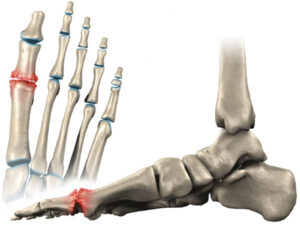

El Hallux Rigidus es una patología que impide la dorsiflexión de la articulación del Hallux (dedo gordo del pie).

Se caracteriza por una artrosis osteofítica, degenerativa y anquilosante de la primera articulación metatarsofalángica. El Hallux Rigidus es uno de los problemas más frecuentes del primer dedo del pie.

- Hipertrofia ósea: Este tipo de sintomatología se manifiesta como una deformidad abultada en la zona del primer metatarsiano. Habitualmente, tiende a confundirse con el famoso “juanete” por su parecido anatómico.

En estadios avanzados, a la hora de caminar no se puede ejecutar el paso correctamente, limitando así la fase en la que el pie despega del suelo (3º rocker o balancín del pie).